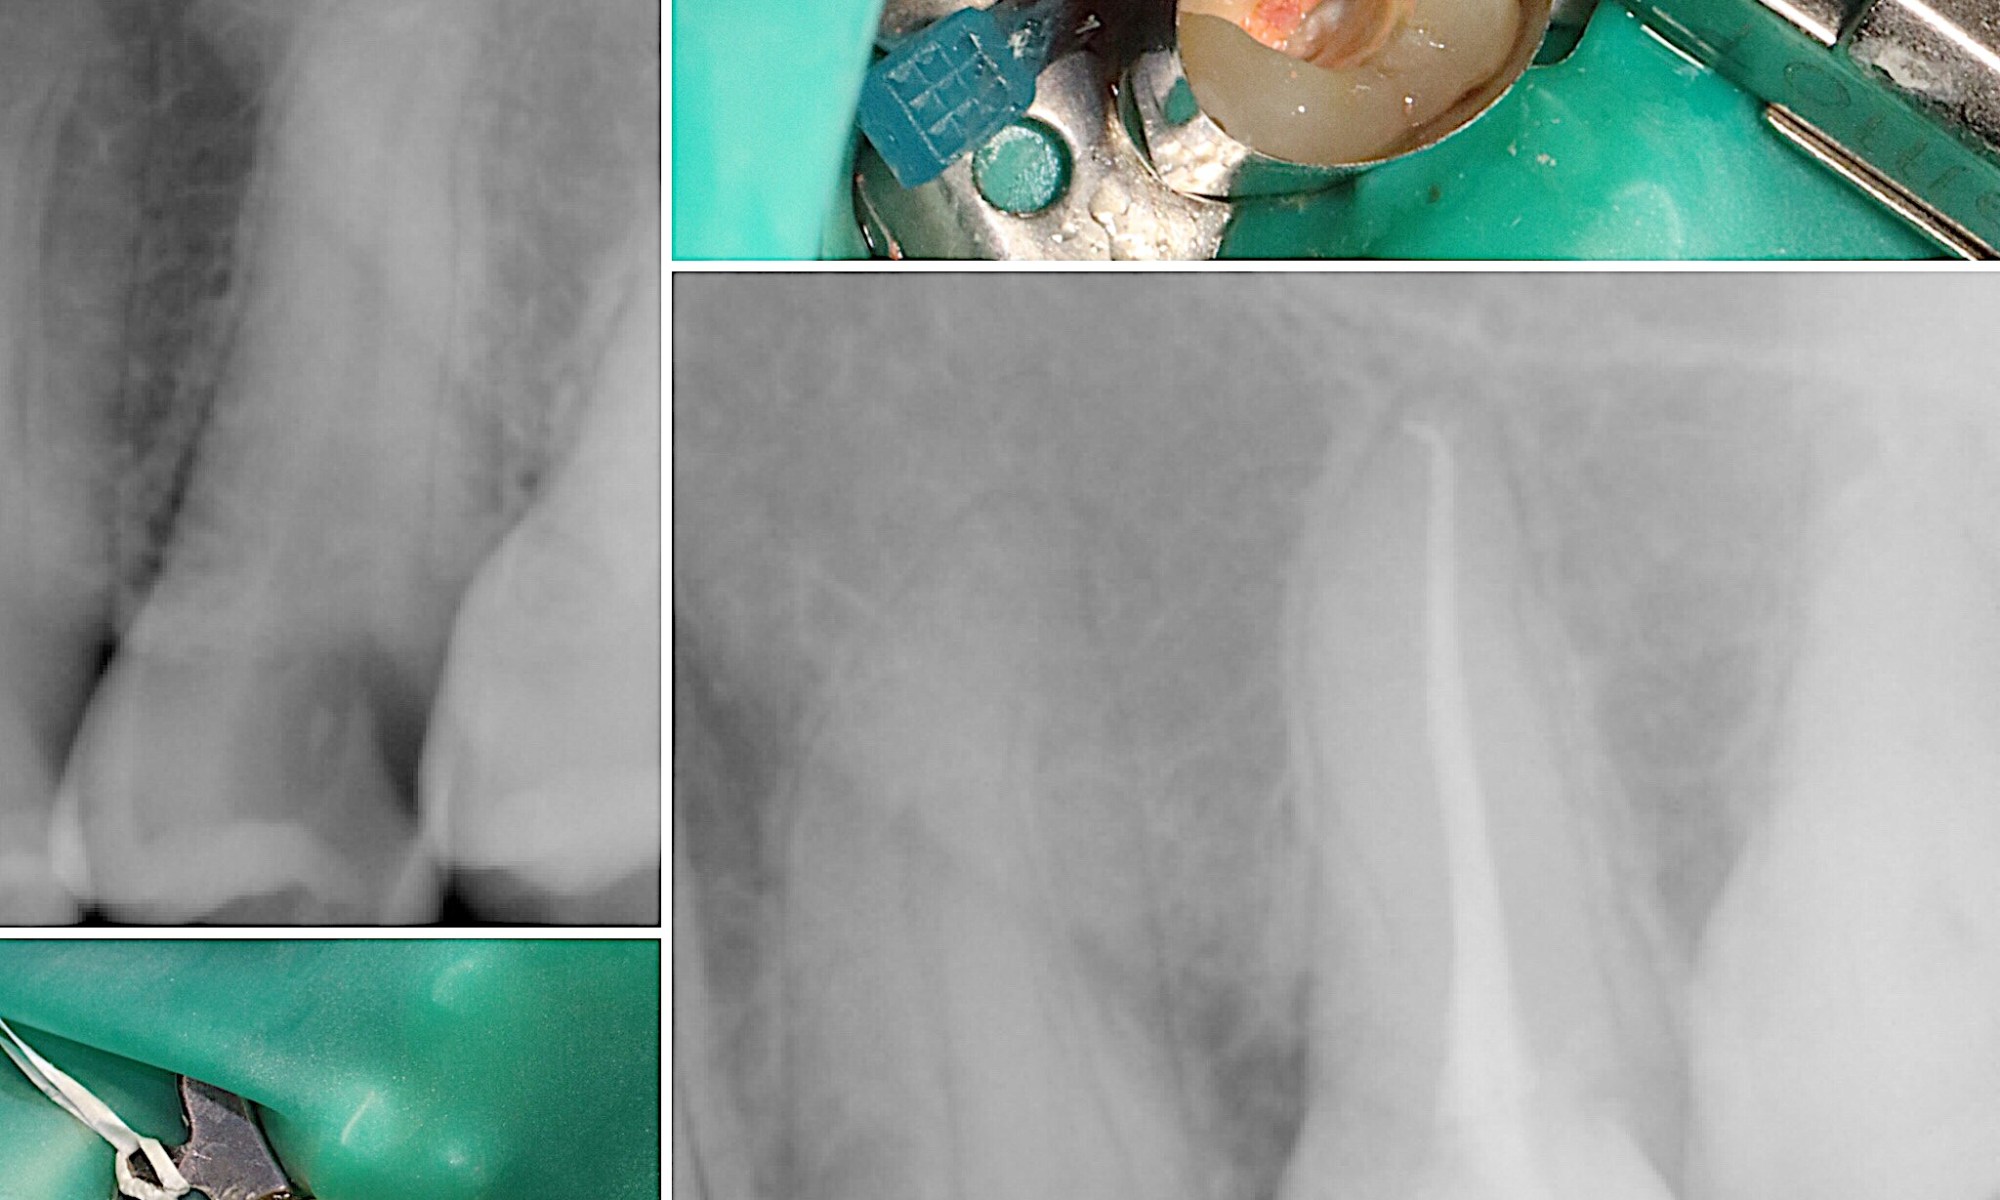

Large cavity caused this patient great grief. We completed the root canal and final restoration. Patient super happy! Related